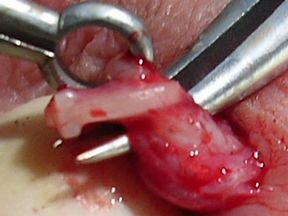

Of the four patients on whom I performed the VasClip procedure in the presence of the founder of the company, two experienced early failure. This 50% early failure rate is not acceptable and I no longer perform the VasClip procedure. The other two patients became sperm-free, but they are aware of the other two early failures and they have been encouraged to have their semen checked periodically for the delayed reappearance of sperm (late failure). The photos below were taken during the repeat vasectomy (on 2/23/05) of a man who had experienced VasClip failure.

Section of the vas with VasClip intact lifted through a small scrotal opening. The section was removed ...

...and one can barely see the opening of the cut vas. Water passed through the vas even before the VasClip was removed, confirming the patency (openness) of the vas.